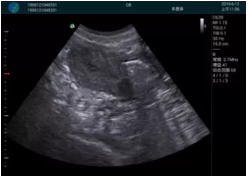

甲狀腺囊性結(jié)節(jié),囊壁鈣化,透聲好

甲狀腺囊性占位